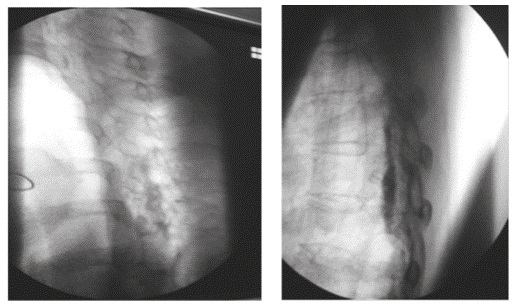

El diagnóstico de certeza del bloqueo subdural es radiológico 20. En el primer caso, guiado por fluoroscopia, se pudo observar, luego de la aplicación del medio de contraste, la distribución subdural en la proyección AP, como una extensa dispersión a varios niveles por encima y por debajo del sitio de inyección, con patrón homogéneo del contraste (Figura 1). En la proyección lateral (Figura 2) se observó una colección densa de medio de contraste con abombamiento a la porción central del canal espinal, que no salía a las raíces espinales laterales o a la porción inferior del saco tecal.

El medio de contraste en un epidurograma normal da un patrón que se asemeja a un árbol de Navidad; su distribución puede ser asimétrica y se observan burbujas dentro de la mancha de medio de contraste, a diferencia del patrón homogéneo del contraste observado cuando la inyección es subdural, donde se distribuye ampliamente a muchos segmentos de la columna vertebral hacia arriba y hacia abajo en una columna estrecha, por lo que la imagen característica se ha denominado ''rieles de ferrocarril'' patrón visto en la proyección anteroposterior, en la que se observan dos finas columnas laterales, resultado de que el espacio subdural es más ancho lateralmente, lo que permite la acumulación allí del contraste, mientras que en la imagen lateral las columnas de contraste se localizan dorsal y ventralmente. Una opacidad mal definida entre las columnas representa un pequeño volumen de contraste subdural 21, como se pudo detectar a tiempo en el segundo caso (Figura 3a), y, de esta forma, evitar las complicaciones de una inyección en el espacio equivocado.